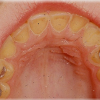

Hamba erosioon

Muu kui katubakterite happe põhjustatud hamba kõvakoe happelist kahjustust nimetatakse erosiooniks. Hape söövitab ehk demineraliseerib hambapinda, muutes selle pehmeks ja nii kiiresti kuluvaks.